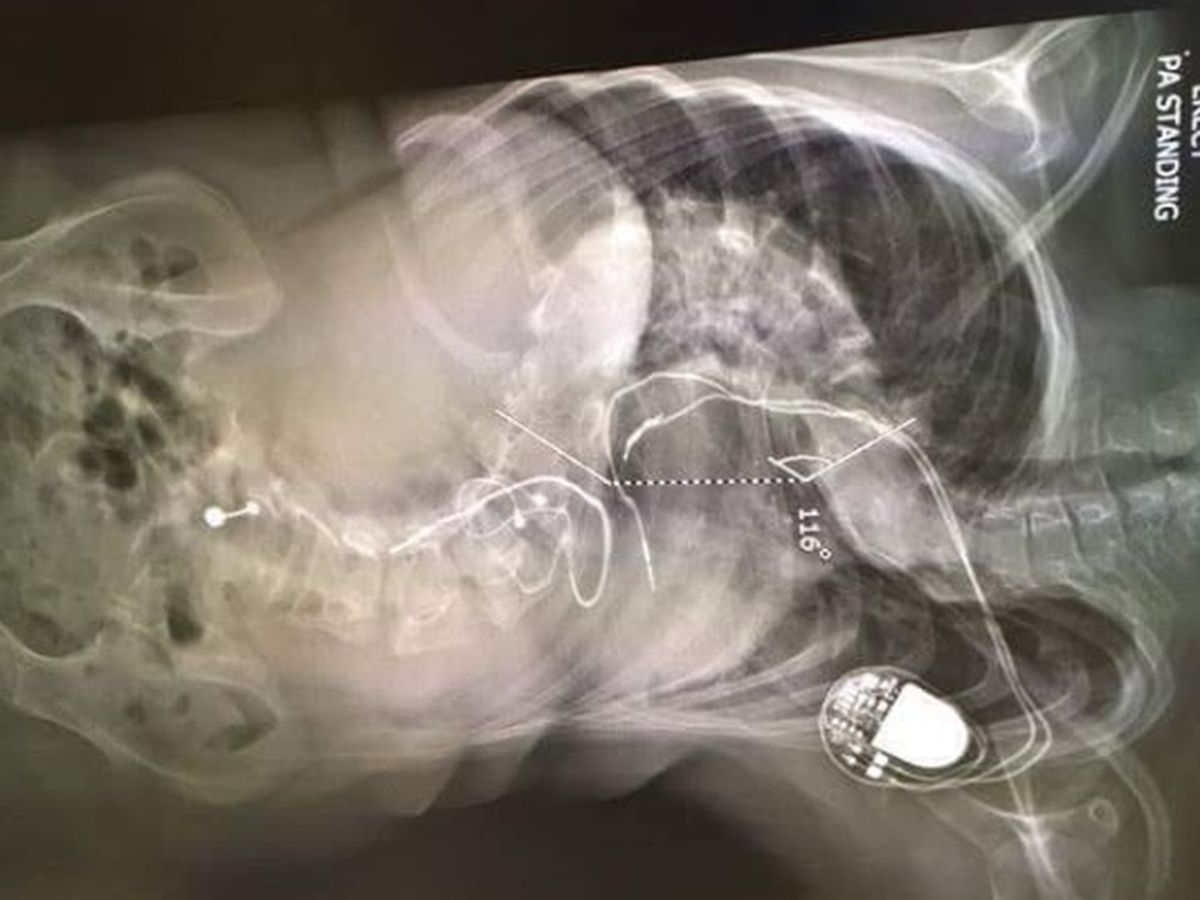

Samantha Harris was diagnosed with scoliosis when She was around 7. She wore a back brace for a few years and then stopped wearing it because of bullying. The curve began to get worse and worse but however because of such low weight She was unable to have the surgery. Then after gaining weight and slipping through the cracks of the system they decided the would do the surgery at the Royal children's in Melbourne the next week. Because of Sams anxiety it was simply to soon to do it and freaked out. They then decided it would be best to transfer Sam to Brisbane where She is living. And going private was the only option as She needs surgery ASAP .

The surgery will involve 3 months in a halo and gravity traction at home...Then after they are happy with how the halo has worked they will do spinal fusion surgery to make sure it won't go back to how it was. Sam is currently on multiple pain medication and finds it hard to walk more the 150m at a time...so the surgery is a must because without it not only will the pain get worse but her spine will crush her organs and Sam will end up in a wheelchair and eventually die without the surgery.